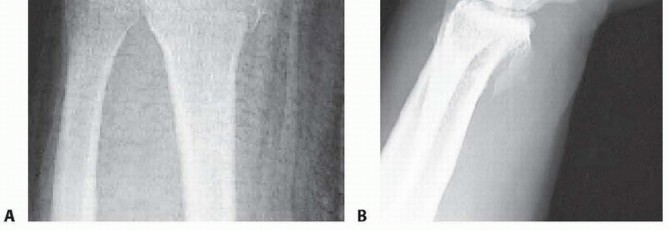

1. Attenuation/hemorrhage of interosseous ligament as seen from the radiocarpal joint. No incongruency of carpal alignment in the midcarpal space. There is a loss of the normal concave appearance between the carpal bones, and the interosseous ligament attenuates and becomes convex as seen from the radiocarpal space. In midcarpal space, the interval between the carpal bones will still be tight and congruent, with no step-off. Immobilization 2. Attenuation/hemorrhage of the interosseous ligament as seen from the radiocarpal joint. Incongruency/stepoff as seen from the midcarpal space. A slight gap between the carpal bones may be present. A slight gap (less than the width of a probe) between the carpal bones may be present. The interosseous ligament continues to become attenuated and is convex as seen from the radial carpal space. In the midcarpal space, the interval between the involved carpal bones is no longer congruent, and a step-off is present. In scapholunate instability, palmar flexion of the dorsal lip of the scaphoid will be seen as compared to the lunate. In lunotriquetral instability, increased translation between the triquetrum and lunate will be seen when palpated with a probe. Arthroscopic reduction and pinning 3. Incongruency/step-off of carpal alignment is seen in both the radiocarpal and midcarpal spaces. The interosseous ligament has started to tear, usually from volar to dorsal, and a gap is seen between the carpal bones in the radiocarpal space. A probe often is helpful to separate the involved carpal bones in the radiocarpal space. In the midcarpal space, a 2-mm probe may be placed between the carpal bones and twisted. Arthroscopic/open reduction and pinning 4. Incongruency/step-off of carpal alignment is seen in both the radiocarpal and midcarpal spaces. Gross instability with manipulation is noted. A 2.7-mm arthroscope may be passed through the gap between the carpal bones. The interosseous ligament is completely detached between the involved carpal bones. This is the “drive-through” sign, when the arthroscope may be freely passed from the radiocarpal space through the tear to the midcarpal space. Open reduction and repair In another study, SLIL injuries were found in more than half, LTIL injuries in one-third, and TFCC in 60%. Only 17% of patients were free of any of the three injuries. 28 Untreated complete tears of the SLIL, which are highly associated with radial styloid fractures, may progress to a wrist with scapholunate advanced collapse. ## PATIENT HISTORY AND PHYSICAL FINDINGS A thorough history should be obtained, including the circumstances surrounding the injury as well as any additional injuries. Neurologic basis Cardiac basis Patients' level of independence, dominant hand, status with assisted devices, work, activity level, and support structure should be determined. Physical examination, while concentrating on the wrist, should also include the hand, elbow, and shoulder to check for concomitant injuries. The hand, wrist, forearm, arm, and shoulder must be carefully inspected for open injury so that tetanus and antibiotic prophylaxis may be initiated if necessary. A thorough distal sensory and motor function examination should be carried out in an organized manner. Vascular examination should include palpation of both the radial and ulnar pulses and determination of capillary refill time. Precise palpation is used to define areas of potential trauma. Diminished sensibility, pallor, altered capillary refill, increased tenseness of the soft tissues, and pain out of proportion should raise suspicion for significant soft tissue injury, including compartment syndrome. ## IMAGING AND OTHER DIAGNOSTIC STUDIES Posteroanterior (PA), oblique, and lateral radiographs are the primary radiographic studies used to workup distal radius fractures. Radiographs of the uninvolved contralateral extremity are useful to compare radial inclination, ulnar variance, and sigmoid notch anatomy. PA projections are useful to evaluate the radial inclination, radius height, presence of ulnar styloid fractures, widening of the DRUJ, widening of intercarpal spaces, and intra-articular involvement ( FIG 1A). Standard radiographic parameters of the distal radius include radial inclination of 22 degrees (range 13 to 30 degrees), radius length of 12 mm (range 8 to 18 mm), and volar tilt of 11 degrees (range 1 to 21 degrees). Ulnar variance should be measured with the shoulder in 90 degrees of abduction, the elbow at 90 degrees of flexion, and the wrist in neutral pronation-supination. A lateral projection is used to assess volar and dorsal tilt of the distal fragment, dislocation or subluxation of the DRUJ or carpus, lunate angulation, and dorsal comminution ( FIG 1B). ![]() |

| * FIG 1 • A. PA radiographic view showing a minimally displaced radial styloid fracture fragment. B. The lateral view shows a complete fracturedislocation of the wrist. A modified lateral radiograph with the beam angulating 10 to 30 degrees proximally improves visualization of the articular surface and evaluation of the volar rim of the lunate facet represented by the anterior teardrop. An additional 30-degree anteroposterior (AP) cephalic projection is useful to evaluate the dorsal ulnar margin of the distal radius. Oblique radiographs are very helpful because major fracture fragments may be rotated out of their anatomic planes. Computed tomography (CT) evaluation, particularly threedimensional CT, can further delineate fragment location, joint compression, and rotation. Magnetic resonance imaging (MRI) evaluation is useful in assessing for associated soft tissue injuries such as TFCC tears, interosseous ligament injuries, and carpal fractures. Radiographic signs that demonstrate that the distal radius fracture is likely unstable and closed reduction would be insufficient include the following 21: Lateral tilt greater than 20 degrees dorsal Dorsal comminution greater than 50% of the lateral width Initial fragment displacement greater than 1 cm Volar translation greater than 2 mm Initial radius shortening more than 5 mm Intra-articular step-off greater than 2 mm Associated ulnar fracture Severe osteoporosis Age older than 60 years ## DIFFERENTIAL DIAGNOSIS Carpal bone fracture Metacarpal or phalangeal fracture DRUJ disruption Essex-Lopresti lesion Interosseous ligament tear Carpal dislocation (perilunate) ## NONOPERATIVE MANAGEMENT Displaced fractures of the distal radius are reduced using an adequate anesthetic agent. Knowledge of the mechanisms of injury helps facilitate manual reduction. Force is applied opposite the force that caused the fracture. Gentle traction is necessary to disimpact the fracture fragments, followed by palmar translation of the hand and carpus in respect to the radius. The radius articular surface will rotate around the intact volar cortical lip to restore volar inclination with palmar translation. Care must be taken to avoid trauma to the skin during the reduction maneuver, particularly in elderly patients where the skin may be fragile. A splint is supplied following the reduction. No consensus has been established regarding wrist or forearm position, longarm versus short-arm immobilization, or splint versus cast. Extreme positions of wrist flexion and ulnar deviation should be avoided. Postreduction radiographs are taken in plaster. Depending on stability of the fracture, most patients treated nonoperatively require weekly visits for the first 3 weeks to monitor fracture reduction. In patients older than 65 years, one-third of initially undisplaced fractures subsequently collapsed to some degree. One study of elderly patients with moderately displaced fractures of the distal radius found that two-thirds of the correction obtained by closed manipulation was lost at 5 weeks. Patients with minimally displaced or nondisplaced fractures of the distal radius treated nonoperatively must be made aware of possible complications, including rupture of the extensor pollicis longus tendon, carpal tunnel syndrome, and compartment syndrome. Elderly patients typically tolerate nonoperative management well. Patients older than 65 years undergoing nonoperative results have comparable results to those that undergo operative treatment despite unsatisfactory radiographic outcomes. 2, 3 ## SURGICAL MANAGEMENT Distal radius fractures without extensive metaphyseal comminution are ideal candidates for arthroscopic- assisted fixation with K-wires or cannulated screws. 14, 15, 22 Radial styloid fractures Impacted fractures Die-punch fractures Three-part T-type fractures and four-part fractures with metaphyseal comminution are best treated with a combination of volar plate stabilization. Wrist arthroscopy is used as an adjunct to fine-tune the articular reduction and evaluate for associated soft tissue lesions. Distal radius fractures that may be minimally displaced, and fractures with strongly suspected associated soft tissue injury, also are candidates for arthroscopic-assisted fixation to stabilize the fracture but, more importantly, to evaluate and treat the acute associated soft tissue injury. Stabilization of associated ulnar styloid fragments is controversial. 20 Wrist arthroscopy provides a rationale as to when to stabilize an ulnar styloid fragment. ## Preoperative Planning All radiographic studies are reviewed. Equipment needed for arthroscopic treatment and for open stabilization is made available. Small joint instrumentation is essential for arthroscopicassisted fixation of distal radius fractures. The small joint |